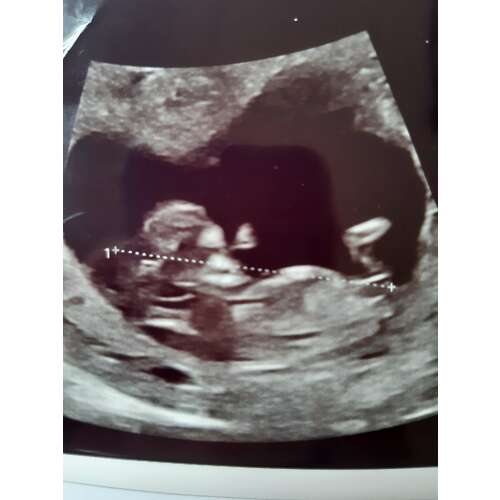

Ik kan mijn originele post niet meer vinden, en staat ook in deel 18 volgens mij, maar wij krijgen een meisje 💓 Ramzi werd meisje gezegd (wel n lastige) en nub werd meisje gezegd. @Nubster, bedankt! 🌹 Ik zal nog even n foto plaatsen van de bevestigde meisjes nub.

Dit is de bevestigde meisjes nub 🥰

Gefeliciteerd!! 💗🎀💞 Dank voor je update ☺️

Ow wat leuk! Toch weer Nubster die t goed heeft!